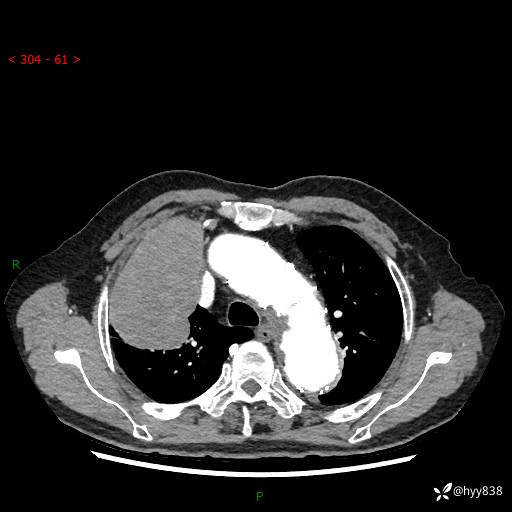

增强动脉期